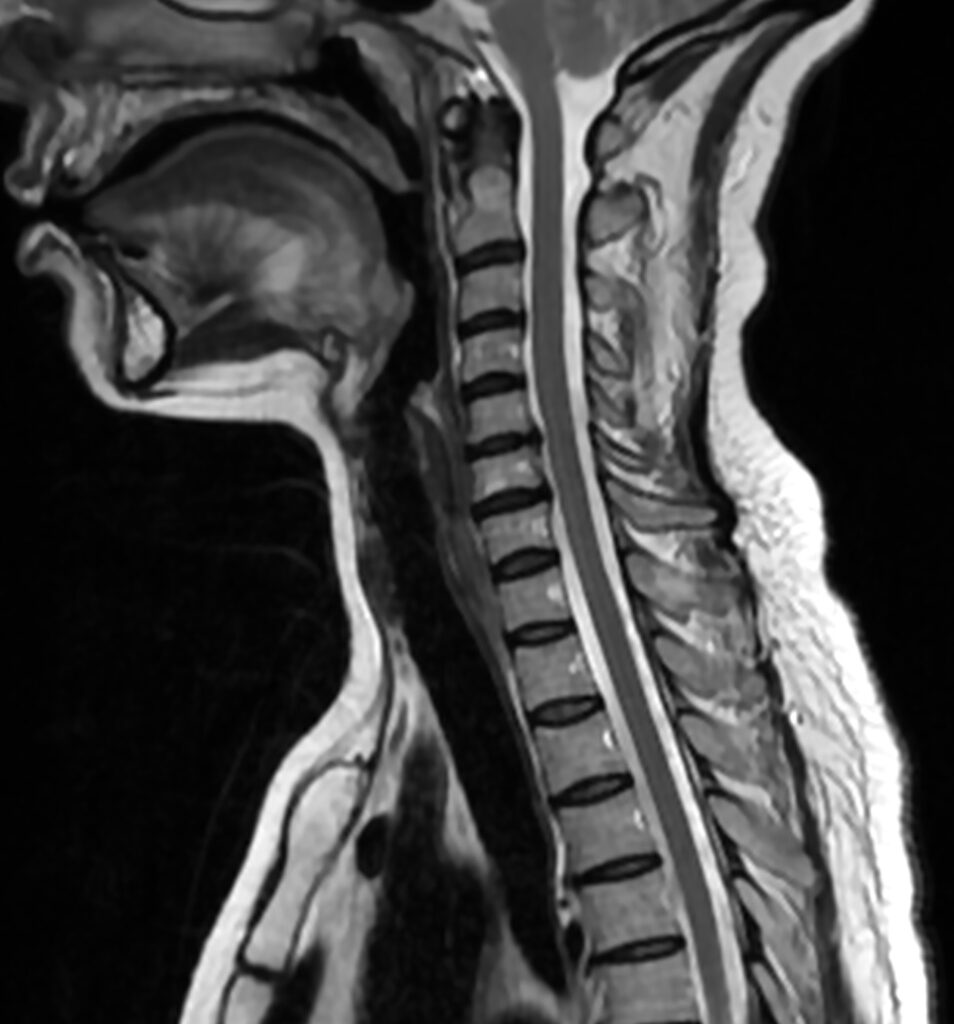

Hernia discal cervical

Algunas veces el dolor cervical se irradia a lo largo del brazo hasta las manos. Esto puede ser debido a una hernia discal cervical que comprime el nervio, y afecta severamente su función.

El dolor por compresión del nervio algunas veces asocia adormecimiento de la mano y pérdida de fuerza. Muchos de nuestros pacientes refieren pérdida de destreza con la mano (tienen menos agilidad con los dispositivos electrónicos o las tareas manuales como abrir un frasco o sujetar una taza).

Otras veces, la hernia puede contactar con la médula, y producir problemas para caminar o torpeza en las piernas y en las manos, precisando una valoración urgente.

Las hernias discales cervicales son un proceso que habitualmente se resuelve espontáneamente. Sin embargo, si existe un dolor muy severo e invalidante y pérdida de fuerza, se precisa de la valoración de un especialista de columna. El neurocirujano indicará las pruebas necesarias para estudiar la causa del dolor, y finalmente, valorar la necesidad de un tratamiento quirúrgico. Afortunadamente, a día de hoy puede extirparse una hernia discal con un abordaje mínimamente invasivo y con una rápida recuperación.